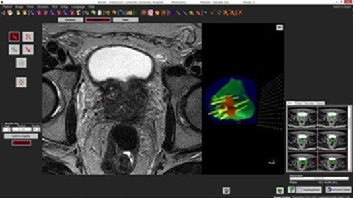

これに対して、今回当院で導入した「バイオジェット」による「標的生検」という手法は、事前にMRI画像を撮影することで、がんができている部位をあらかじめ確認し、前立腺に生検針を刺す際の超音波画像にソフトウェア上で事前のMRI画像(がんの疑いのある部位が特定できた画像)を重ね合わせた画像イメージを合成し、針を刺すべき場所を教えてくれるシステムです。これにより、効率よく正確に疑わしい部位から組織を採取することができます。